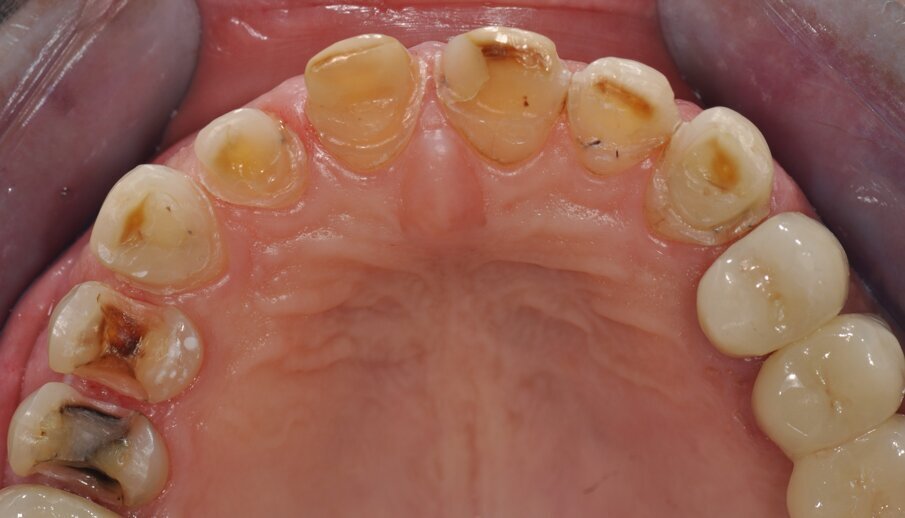

Fig. 1: Clinical baseline situation

A 55-year-old woman presented at the Department of Preventive Dentistry, Periodontology and Cariology of the University of Göttingen. The clinical and radiological examination revealed an adult dentition that had been insufficiently treated with fillings and dental restorations and exhibited a loss of vertical dimension of occlusion (Figs. 1 and 2). Insufficient restorations (secondary caries) were found on teeth 24, 25, 26, 27, 37, 38, 35, 47, and 48. The existing bridge (17–15, 14) was insufficient due to extensive ceramic fractures. Part of the hard tissue of the upper maxillary incisors with their — sometimes extensive — composite restorations had been lost to attrition and vestibular erosion. The endodontic treatment of tooth 34 was adequate, while tooth 46 required a primary endodontic treatment due to an irreversible pulpitis. All other teeth were vital and free of symptoms. The periodontal findings showed moderate gingivitis (periodontal screening index < 3 in all sextants). Teeth 13, 23, 24, and 43 additionally exhibited vestibular gingival recessions.